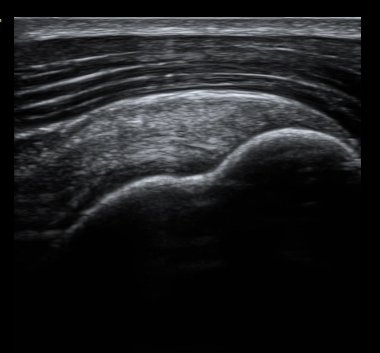

ȸÀü±Ù°³°£°Ý ³»Ãø Ⱦ´Ü¸é°Ë»ç¿¡¼­ °üÂûÇÑ °ß°©ÇÏ±Ù°Ç »óºÎ Á¾´Ü¸é°Ë»ç¿¡¼­ ¹Ì¼¼ÇÑ °£±ØÀÌ

°üÂûµÊ(±×¸² 3, 4). °ß°©ÇÏ±Ù°Ç È¾´Ü¸é°Ë»ç¿¡¼­µµ °ß°©Çϱٰdz» °£±ØÀÌ °üÂûµÊ(±×¸² 5).